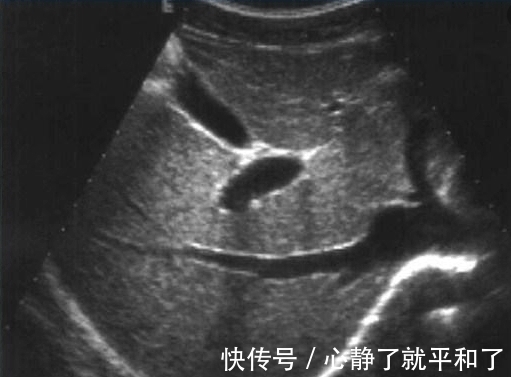

以前一个患者家属来咨询我说父亲前几天在乡下抽血体检一切都是正常的。但总觉得长期腹胀痛并伴有消瘦所以来我们医院做一下更全面的检查。结果做了胃镜发现是胃癌,作为全腹 CT 平扫还发现肝脏有一个转移的小结节。

后来我看了患者的乡下体检报告,其实他在乡镇卫生院就做了抽血的全套体检,胸片和心电图等简单的体检,并没有作胃镜、肠镜、全腹彩超、双肺部CT及全腹CT等进一步的体检检查,所以肝脏的小结节会漏诊。没体检胃镜胃里面癌症也就漏诊了。

【 体检|为什么体检结果一切正常,4天后查出癌症晚期?】目前临床上消化道道肿瘤占据所有肿瘤一半以上,早期的食管癌、胃肠道癌症只能通过胃肠镜检查出来,其它检查比如彩超、 CT、磁共振等检查都查不出早期的胃肠癌及食管癌,所以常规全面体检也要包含胃肠镜的检查。